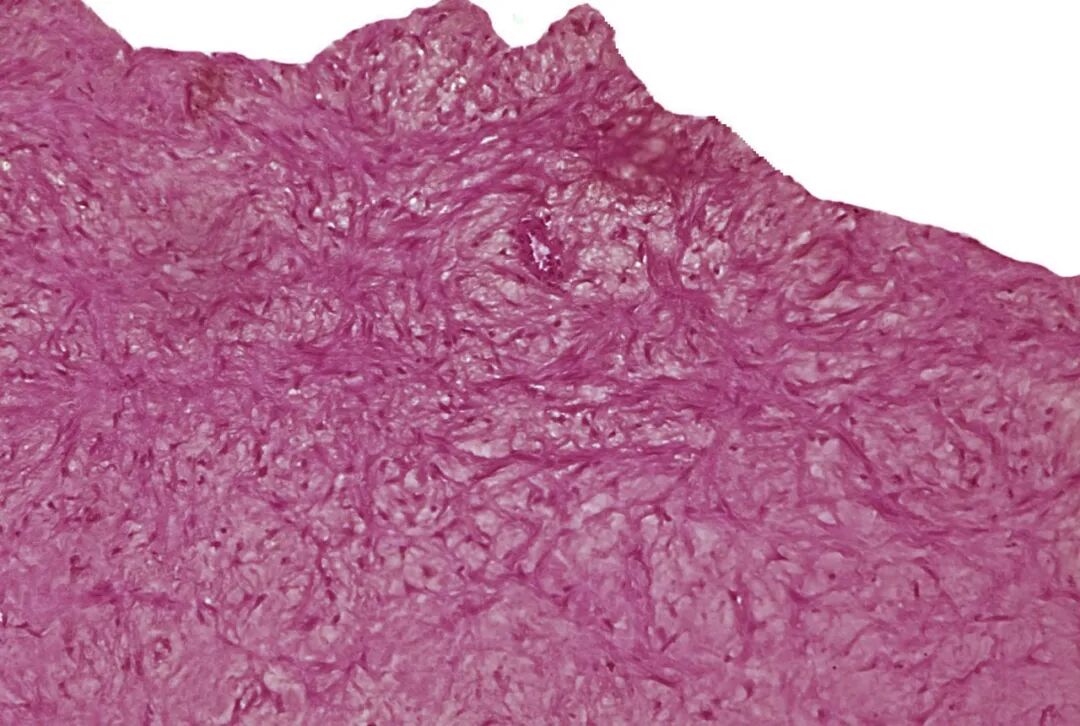

结节性钙化是最具挑战性的一种,常见于CKD患者。组织学上可见成骨细胞、骨小梁甚至骨髓腔。常规球囊扩张时,结节像“石头”一样突出于管腔,导致球囊破裂或严重不对称扩张。活检钳提取和DECIAP是目前少数有效的腔内减容手段。压裂技术虽能使结节产生裂纹,但难以彻底碎裂。

外周动脉疾病患者中钙化结节与斑块破裂的分布:一项血管内超声分析。

通讯作者单位:兵库医科大学,日本兵库县

钙化结节与斑块破裂的代表性血管内超声图像。钙化结节为一团突入动脉管腔内的圆形钙化组织(a)。斑块破裂则表现为一个与管腔相通的空腔(星号标记),其上覆有残余的纤维帽碎片(b)。